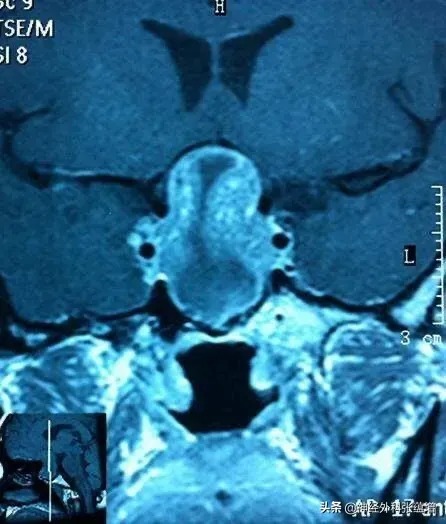

热心肠的张院长分析了他的基本情况可以考虑符合脑垂体瘤的存在,故建议他到医院做一个头颅核磁共振(MRI)检查。第三天他将检查的片子拿给张院长看,结果确实有一颗鸡蛋大小的垂体腺瘤。后经神经外科手术切除肿瘤后治愈。术后了解这一过程的人开玩笑地说:“没想到,神经外科专家张蕴增的司机倒车压扁一个锅,竟“压”出一个脑瘤患者!